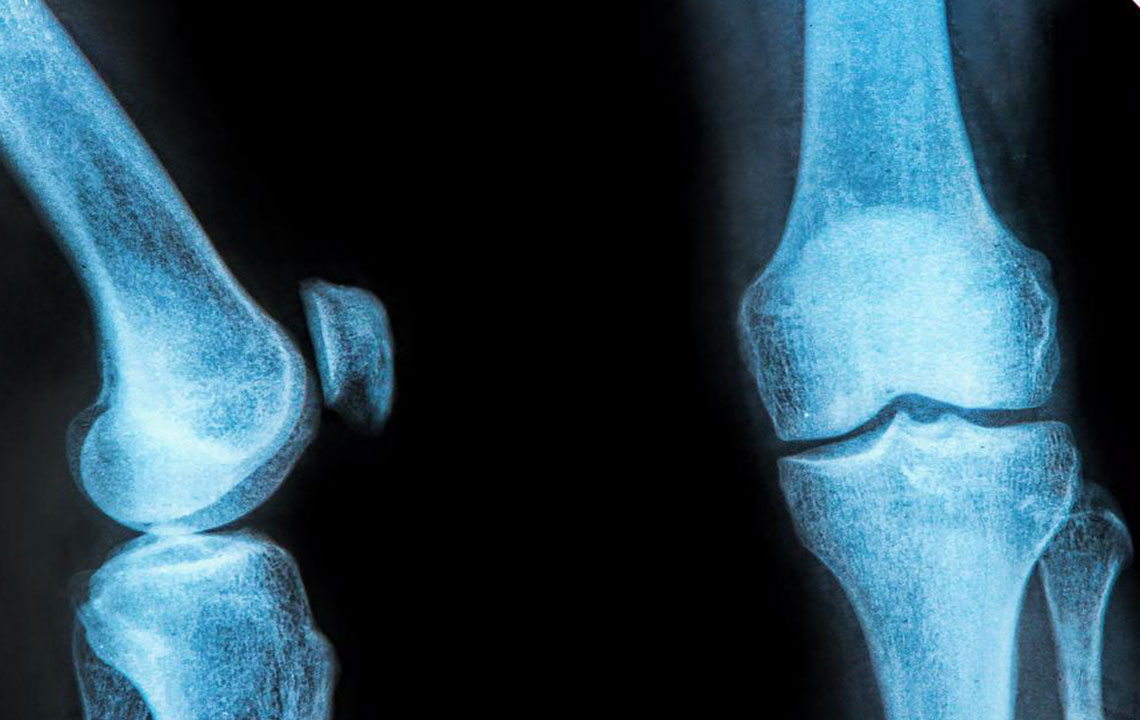

The rubbery C-shaped disc cushioning your knee is a meniscus. There are two menisci in each knee. One at the inner side and the other on the outer side. It is this meniscus that helps to keep your knee steady. It balances your body weight around your knee. If there is a tear in the meniscus, you will experience a lot of pain. It will also prevent the proper functioning of your knee. This kind of a painful injury to the knee is called meniscus tear. It can damage your knee permanently. A brace for meniscus tear can ease your pain.